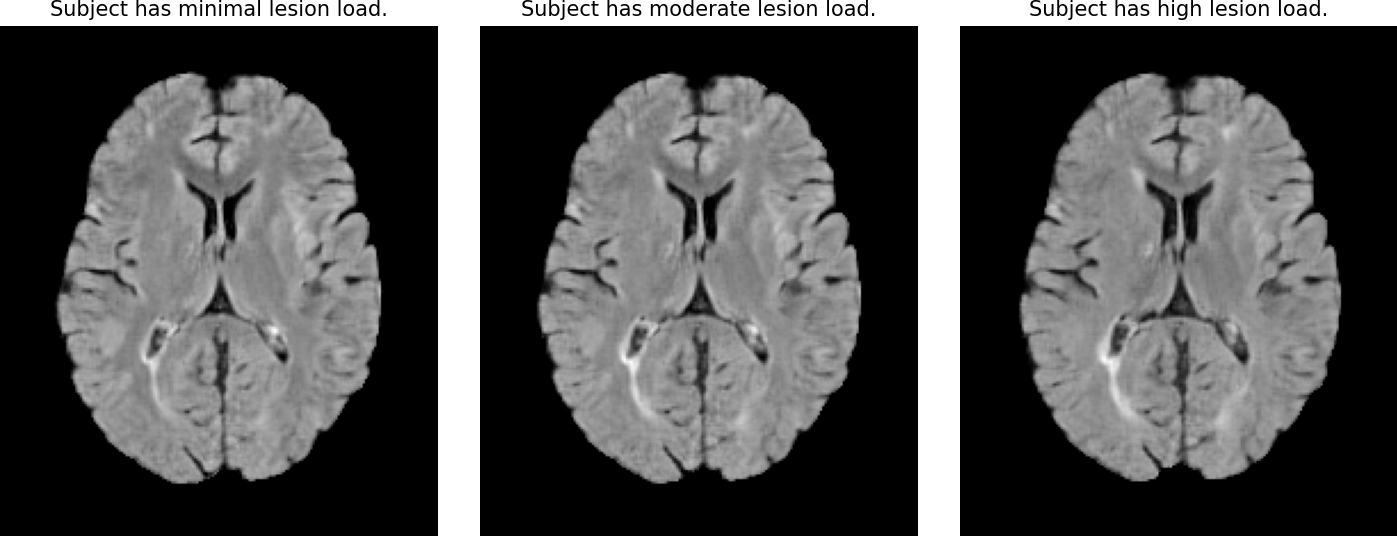

• First research result visualization Fig. 1. Proposed Framework. A pretrained BiomedCLIP text encoder encodes the text prompt (e.g. “Subject has high lesion load”) as conditioning for the diffusion model. During inference, the model generates counterfactuals by sampling from the same fixed noise while varying the text condition.

Vision-language models have shown strong performance in 2D image generation due to extensive pretrained foundation models, but comparable models for 3D are lacking, limiting progress in medical imaging. This absence restricts applications such as counterfactual explanations, disease progression simulations, and medical training. We present a framework that generates high-resolution 3D counterfactual medical images from free-form language prompts by adapting state-of-the-art 3D diffusion models with enhanced text conditioning. To our knowledge, this is the first language-guided native-3D diffusion model applied to neurological imaging, enabling faithful representation of brain structures. Experiments on MRI datasets demonstrate the ability to simulate lesion loads in Multiple Sclerosis and cognitive states in Alzheimer’s disease, producing realistic images while preserving synthesized subject fidelity. Our work establishes a foundation for prompt-driven disease progression analysis in 3D medical imaging.